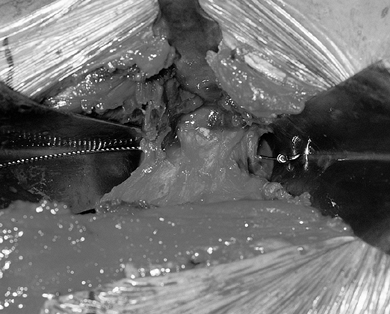

superior pubic ramus with a Gigli saw (Fig. 104.10).

Figure 104.10. Perform an osteotomy of the superior pubic ramus by exposing it through the incision (Fig. 104.8, Fig. 104.9)

and placing dual retractors around the pubic bone. A Gigli saw has been

passed around the pubic bone and will be used to cut it safely from

posterior to anterior. -